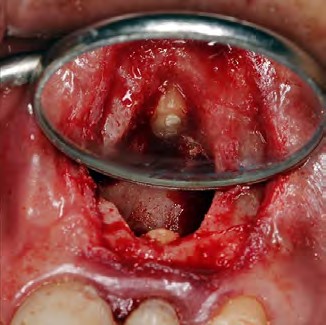

Después de la asepsia y antisepsia de la zona quirúrgica, se procedió con el bloqueo del nervio alveolar superior anterior y nervio nasopalatino (lidocaína 2% con epinefrina 1:80 000 Xylestesin, 3M ESPE, GERMANY), se realizó una incisión paramarginal con una hoja de bisturí #15 y posterior elevación del colgajo de espesor total. Ya expuesta la raíz (Fig. 2), se realizó la enucleación de la lesión, limpieza del campo quirúrgico mediante una fresa redonda de carburo tungsteno y rectificación del corte apical corrigiendo el bisel anterior por un bisel de 0° (Fig. 3). Con una gasa estéril impregnada de anestésico con vaso constrictor, se aplicó para el control de la hemorragia.

Figura 2. Primera exposición del área periapical.